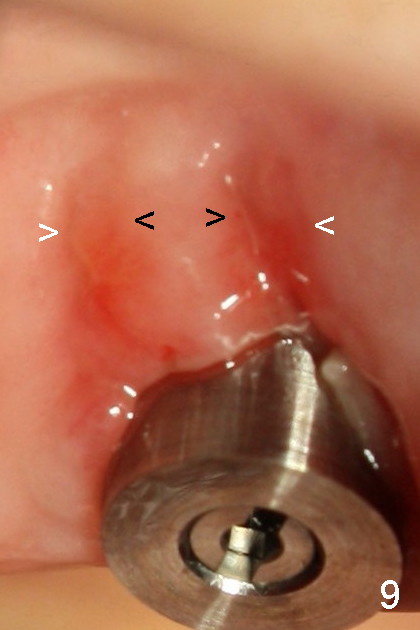

Fig.9 (magnified image, one week post immediate implantation): The mesiobuccal and distobuccal sockets have apparently been healing. The gingiva appears to grow from the septum (black arrowheads) and nearby gingiva (white arrowheads).